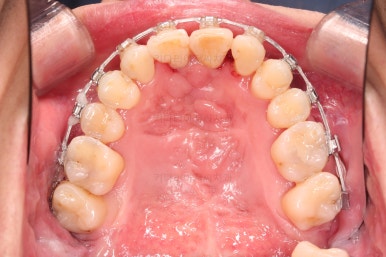

초기 단계의 주안점은 아랫니와 악궁과 어울리는 윗니 악궁의 형태를 만들어 주는 것이고요.

악궁확장장치를 사용하지 않은만큼 철사의 형태를 잘 잡아가면서 악궁 형태를 개선시킵니다.

교정 10개월째인데, 악궁형태 많이 좋아졌고, 가지런한 느낌도 많이 좋아졌습니다.